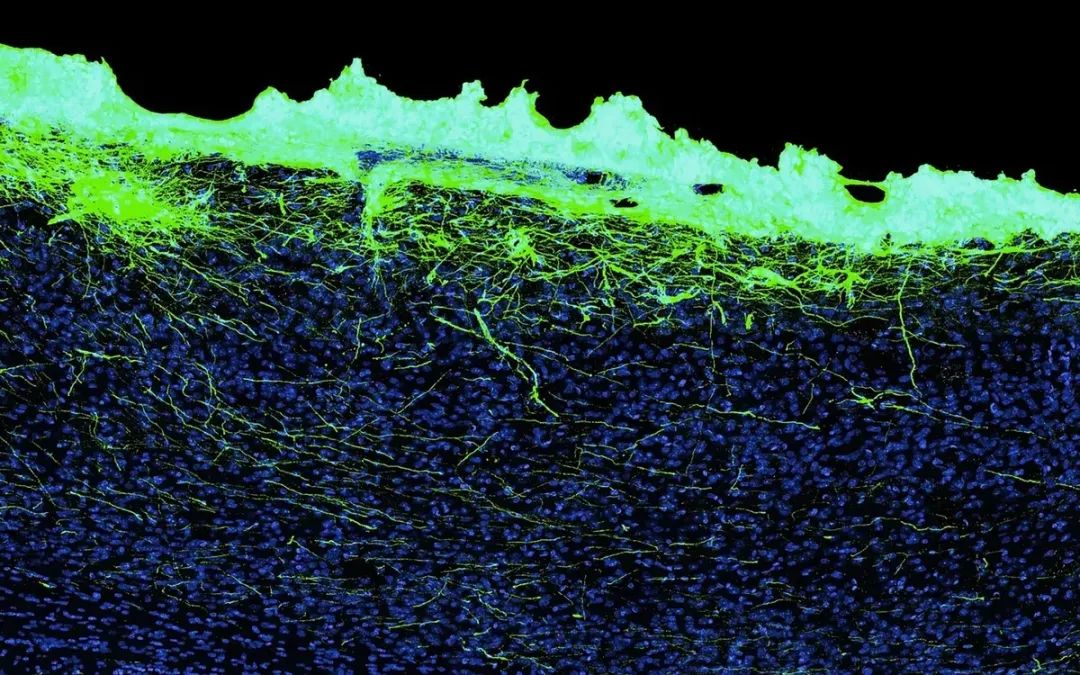

植入生物混合装置(绿色)数月后,神经元长入脑组织(蓝色)。Science Corp

科学公司的设备并没有将任何东西植入大脑,而是放在大脑上面。但这种设备并不仅仅是一块贴在大脑表面的板子——它充满了神经元。神经元位于一个类似华夫饼的装置的孔中,然后附着在大脑表面,神经元朝下。神经元向下生长进入大脑,充当设备和大脑组织之间的粘合剂。

该装置看起来像一个华夫饼,上面有一个个被称为微孔的小碟子,每个直径为 10 微米,安装在透明底板上。每个微孔容纳一个神经元,每个装置约5毫米见方,平均容纳9万个神经元。生物混合装置中的神经元长到了大脑皮层的最顶端,血管也长到了新的神经元中。

植入物下的大脑图像显示,神经元轴突穿过大脑最表面的致密细胞层,进入大脑皮层的第一层。